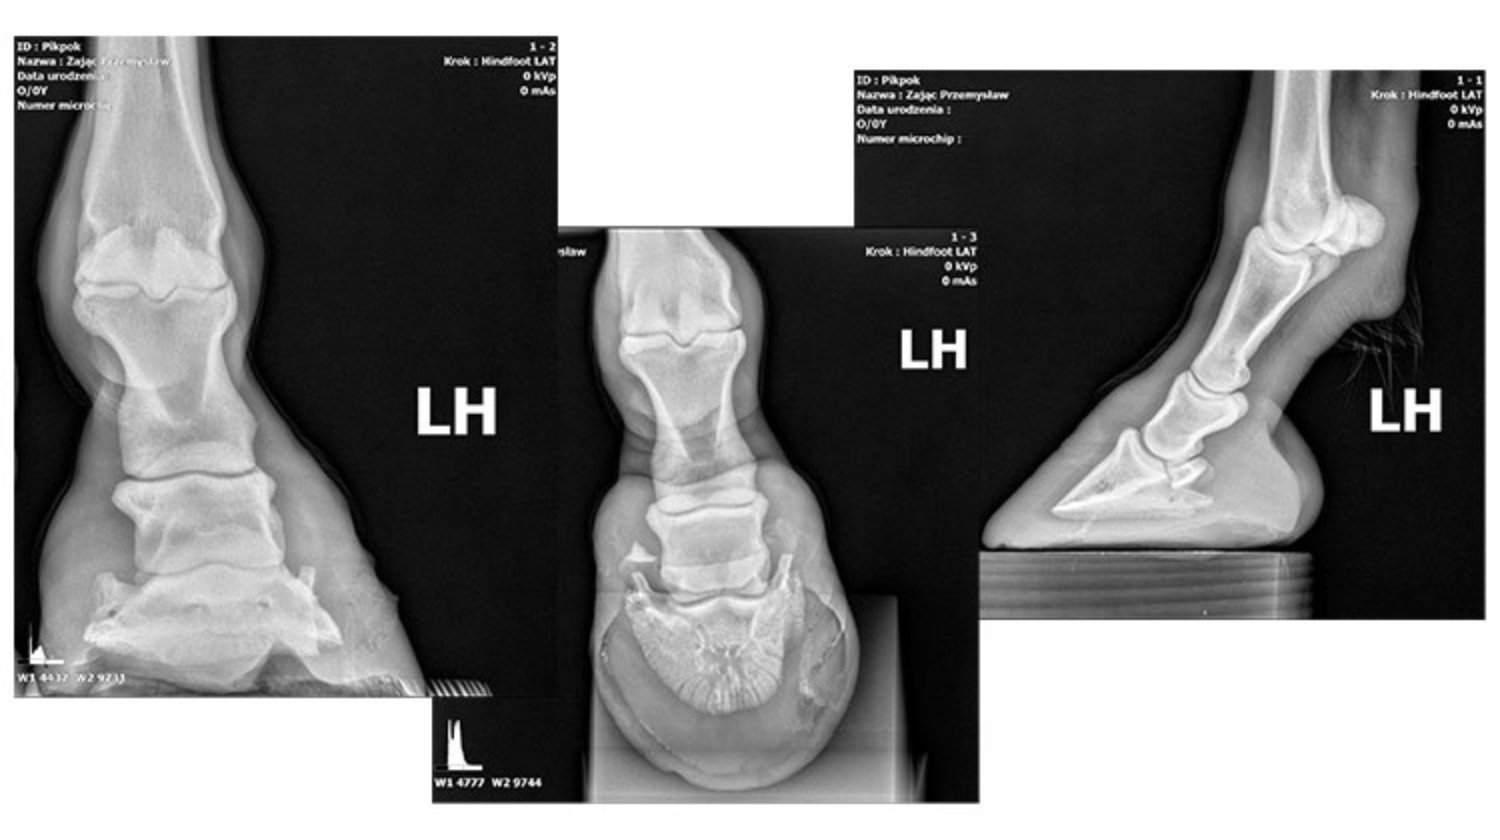

Pikpok od początku roku walczy z bólem kopyta, gdzie zbierała się ropa. Mimo prób leczenia problem powracał, a kolejne badania nie ujawniały jednoznacznej przyczyny. Ostatecznie lekarze postawili diagnozę – słupek rogowy w kopycie, wymagający operacji w specjalistycznej klinice.

Koszty operacji i rehabilitacji są wysokie, a Stowarzyszenie „Serce Hucuła” nie dysponuje pełnym budżetem na leczenie Pikpoka. Dlatego powstała zbiórka na platformie Zrzutka.pl, licząca na wsparcie osób dobrej woli, które chcą pomóc konikowi wrócić do zdrowia i dalszej pracy w hipoterapii oraz nauce jazdy konnej.